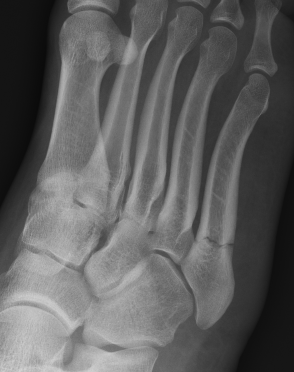

Operative management

Indications

- displaced fractures > 2 mm

- nonunion

- athlete

Displaced fracture Nonunion

Options

Intramedullary screw

Plate fixation

- systematic review of 10 studies and 300 patients

- screw versus plate

- no difference in outcomes or complications

Screw fixation Zone 2 nonunion

Screw fixation Zone 3 nonunion